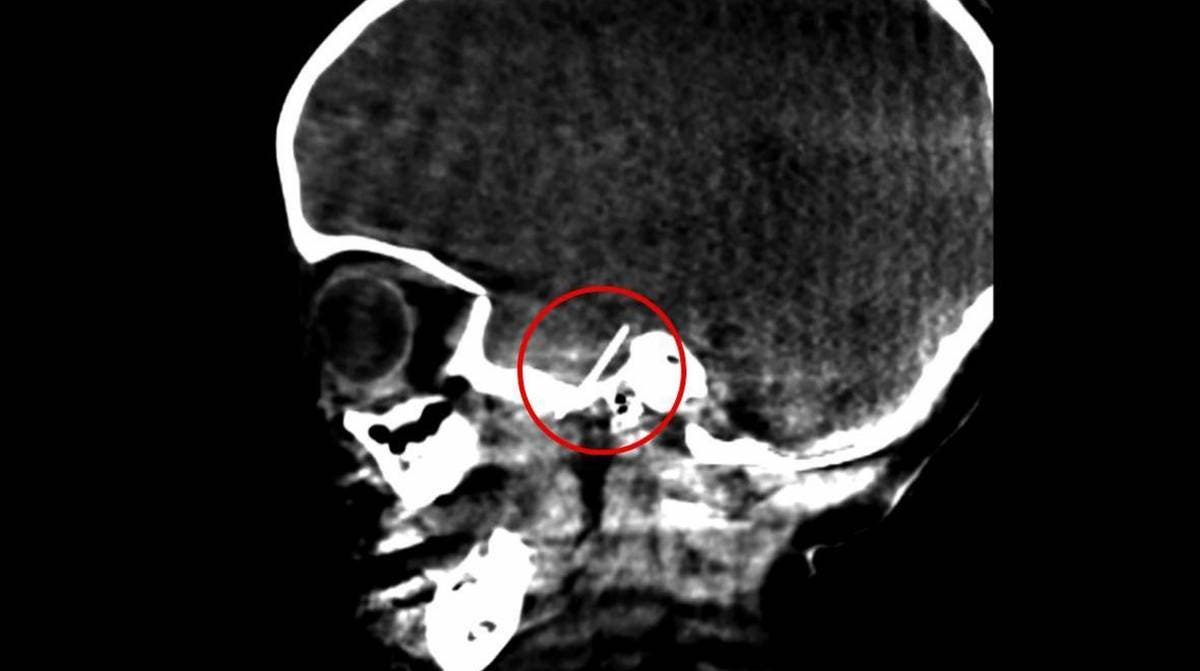

La riesgosa operación fue llevada a cabo por los doctores Josep Rubio, cirujano maxilofacial pediátrico, y José Hinojosa, neurocirujano pediátrico, consiguiendo sacar la aguja anestésica de dentista que había llegado al cerebro de la pequeña, la intervención fue exitosa y la niña de cuatro años se ha recuperado sin ninguna secuela neuronal o daño cerebral.

De acuerdo con el testimonio de la madre de la niña para un medio digital, La mujer habría llevado a su hija con un dentista por una caries, pero la aguja de la anestesia se quedo atorada en el momento de la aplicación, llegando hasta el sistema nervioso de la niña.

La madre notó de inmediato que, al momento de extraer la jeringa de la boca de la niña, no salió la aguja. Los padres sumamente preocupados buscaron otros dentistas para pedir ayuda, pero los dentistas a los que acudían entre más tocaban la aguja, más de adentraba al cerebro de la pequeña, hasta que finalmente uno contactó por un consejo al doctor Josep Rubio el jefe de cirugía maxilofacial del Hospital Sant Joan de Déu.

De acuerdo con lo dicho por la familia, la cirugía fue muy delicada pues la aguja se había colado por uno de los orificios pequeños donde pasan los nervios y arterias.

En la intervención los especialistas realizaron una incisión pequeña del lado derecho de la cabeza para poder extraer la aguja. Luego de la operación la niña estuvo una semana bajo observación en el hospital, con una buena evolución los cirujanos consideraron que no presentaba alguna secuela posterior, solo una cicatriz.